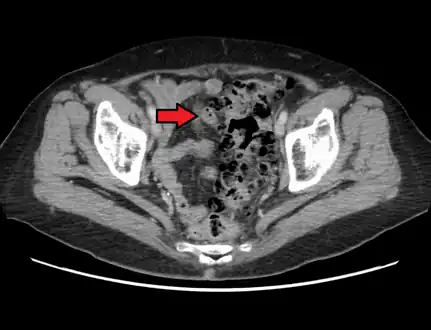

CT scan showing extensive diverticulosis of the sigmoid colon

Diverticular disease

Whole slide of a transverse section of the left colon with diverticulosis

Diverticulosis is defined by the presence of multiple pouches (diverticula) in the colon.[22] In people without symptoms, these are usually found incidentally during other investigations.